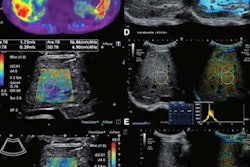

Researchers led by Dr. Scott Crawford from the University of Wisconsin found that shear-wave elastography is helpful in measuring stiffness of the free tendon in patients with chronic midsubstance Achilles tendinopathy. Image courtesy of Dr. Scott Crawford, PhD.The group found significant differences in shear-wave speed in the free tendon between the contralateral and symptomatic limb. The difference was 0.56 m/s, with the symptomatic leg showing slower speed (p = 0.03). Crawford noted that the differences in shear-wave speeds seen in the free tendon and healthy controls in this study were larger than that of the free tendon and contralateral limb as reported in previous research.